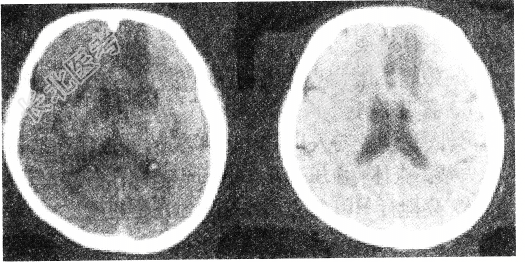

- 单项选择题头颅CT出现如图所示脑梗死,该病灶最可能是以下哪条阻塞引起

A、脉络膜前动脉

B、大脑前动脉主干

C、颈内动脉主干

D、豆纹动脉

E、大脑中动脉主干